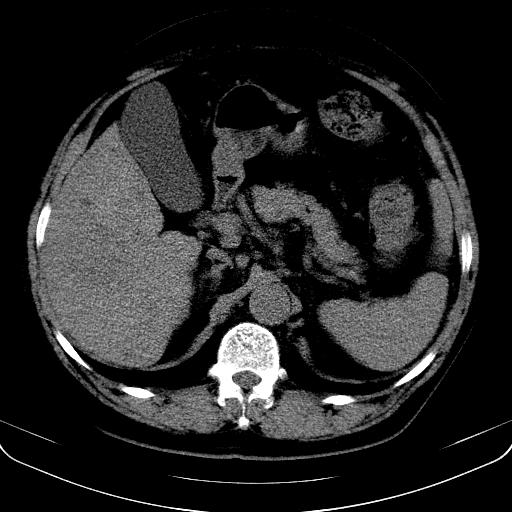

以下是引用jia119在2008-3-5 13:31:00的发言:[br]肝内多发片状低密度影,密度不均,我还是考虑肝ca可能,另肝内小囊肿,胆囊增大。

以下是引用形影不离在2008-3-5 12:18:00的发言:[br]肝硬化伴门脉高压征,肝内占位待排,增强再说.

以下是引用随光逐影在2008-3-5 21:11:00的发言:[br]肝硬化伴门脉高压(食管下段静脉曲张),肝癌不排除。建议:行ct增强扫描检查。

以下是引用同在2008-3-5 13:56:00的发言:[br]考虑肝癌可能性大,胆囊增大.